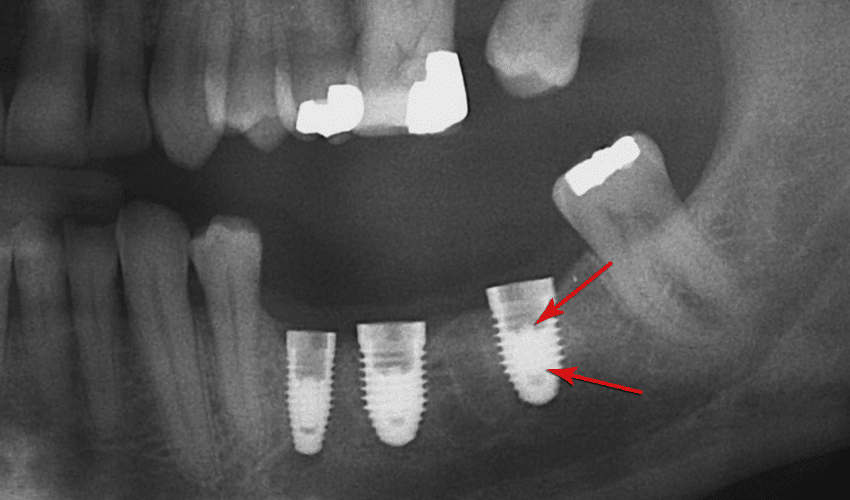

Precise placement of dental implants is essential for their long-term success. If an implant is misaligned during placement, it can create stress on the surrounding bone and tissues. This stress may result in implant failure over time. Working with an experienced and skilled implant dentist is crucial to ensure accurate placement and alignment.